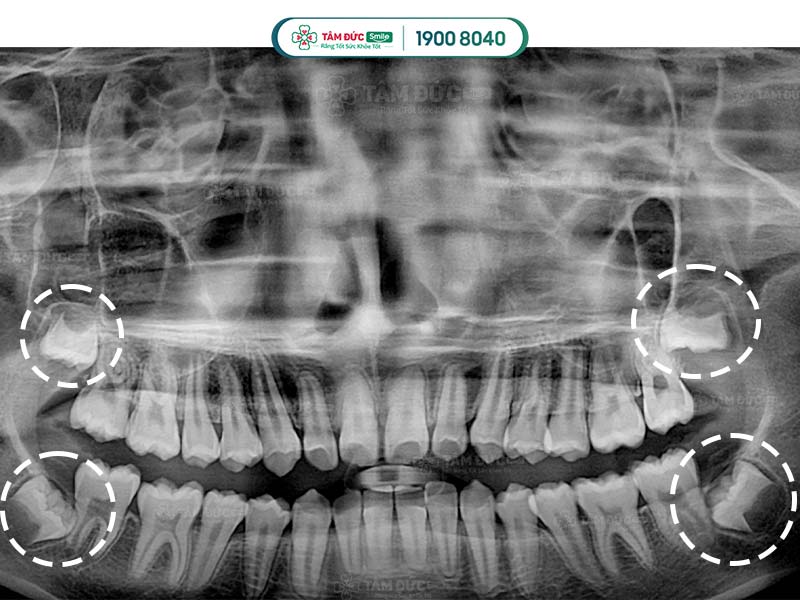

Người trưởng thành thường có 32 chiếc răng. Trong đó bao gồm 4 chiếc răng khôn: 2 răng ở hàm trên và 2 răng ở hàm dưới.

Thời gian răng khôn mọc ở từng người sẽ khác nhau. Thông thường, mọc răng khôn diễn ra khi Quý khách trong độ tuổi từ 17 đến 30 tuổi.

Người trưởng thành có tất cả 4 răng khôn